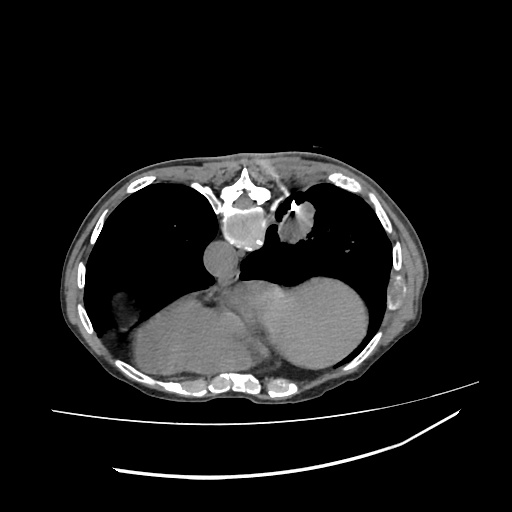

LUNG MASS BIOPSY, 45Y F

LUNG MASS BIOPSY, 70Y F

PANCRATIC BIOPSY, 34Y M